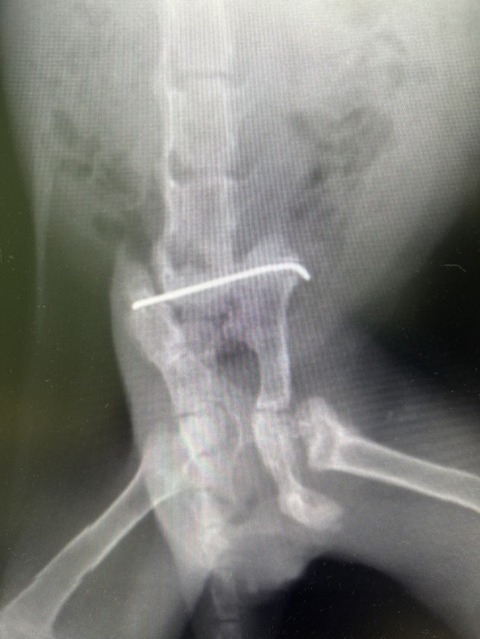

話をよく聞くと

骨盤骨折だったみたいで

開業医に

手術をしてもらったとの事

手術した開業医の話では

骨盤骨折をして

時間が経っていたから

この位置に

ピン留めをしたのだそう

うちに来てから

院長に

レントゲンを撮ってもらったら

確かにピン留めされてる!

そもそも骨盤骨折は

そのままにしておけば

自然と

歩けるようになるのに・・・

あ〜あ・・・

わざわざ麻酔をかけて

切ってピン留めして縫って・・・